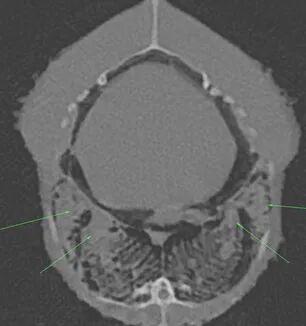

CT平扫:

躯干平扫:双侧肺部存在明显CT值升高区域,右侧较严重。体腔脏器周边存在较多CT值约2HU的均一性物质。肝脏CT值约40HU,肝脏轮廓略钝圆。后腔静脉直径最粗处约10mm。心脏轴面约26*23mm。